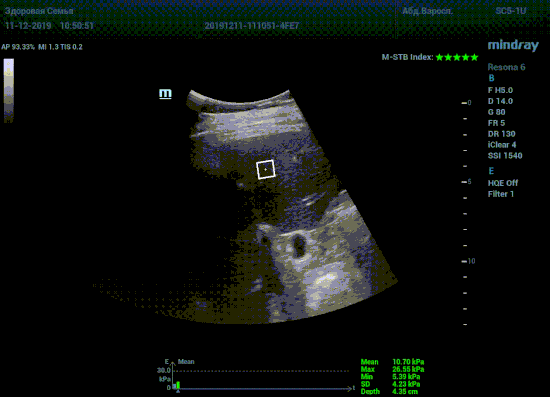

Определение плотности печени. Не ошибся ли оператор при измерении эластических свойств печени? Для оценки критериев качества предусмотрен индекс MBT, который покажет насколько «твердой» была рука оператора и двигалась ли печень. При MBT 5* рука тверда и показатели достоверны. Для оценки качества результатов используется IQR индекс, отображающий колебания показателей в точке измерения при расчете медианы. Показатели при IQR <30% считаются приемлемыми. Техника сканирования через межреберные промежутки требует размещение окна интереса на несколько сантиметром ниже капсулы, для исключения эффекта реверберации. Установка ROI на паренхиму без захвата сосудов, для исключения погрешностей измерения.

Стадия фиброза определяется по системе METAVIR Staging, построенной на данных биопсии и сопоставлении с данными эластографии. Своевременная диагностика фиброза, и начало его лечения, залог благоприятного исхода заболевания.

• METAVIRF0 – норма.

• METAVIRF1 – Портальный фиброз без вовлечения перегородок

• METAVIRF2 – Портальный фиброз с вовлечением нескольких перегородок

• METAVIRF3 – Портальный фиброз с вовлечением множества перегородок

• METAVIRF4 – Цирроз.